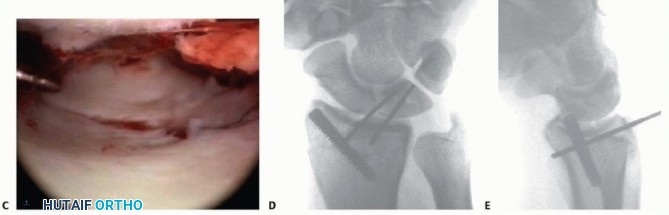

TECH FIG 1 • A. Arthroscopic view of the patient whose radiographs are seen in FIG 1. The arthroscope is in the 6R portal looking across the wrist, and a blunt trocar is in the 3-4 portal. The displaced radial styloid fragment is well visualized. B. A combination of joysticks inserted into the radial styloid fragment and a trocar inserted into the 3-4 portal allows anatomic reduction of the displaced radial styloid fragment and radiocarpal joint. C. The radial styloid fragment is anatomically reduced (with no residual rotation) and stabilized. D. PA view demonstrating anatomic reduction to the radial styloid fragment. Headless cannulated screws are used, if possible, to avoid soft tissue irritation. E. Lateral view showing anatomic restoration to the radial styloid fragment and restoration of the carpus in line with the radius. Suspend the wrist in a traction tower and establish the standard arthroscopic portals. Insert the scope in the dorsal 3-4 portal and clear the joint of debris and hematoma. Transfer the arthroscope to the 6R or 4-5 portal to look across the wrist and effectively judge rotation and reduction of the radial styloid fragment. Using the previously placed guidewires as joysticks, manipulate and anatomically reduce the fracture fragment under direct arthroscopic observation. A trocar can be inserted through the 3-4 portal to help further guide the reduction of the radial styloid fragment ( TECH FIG 1A,B).

Once the fracture is judged to be absolutely anatomic, the guidewires are advanced across the fracture site into the radius shaft and evaluated under fluoroscopy ( TECH FIG 1C). In many cases, the fracture reduction may look anatomic under fluoroscopy, but when viewed arthroscopically, the radial styloid fragment is seen to be slightly rotated. 2 Guidewires alone can be used to stabilize the fracture, but cannulated screws (with or without heads) are recommended ( TECH FIG 1D,E). Cannulated screws decrease soft tissue irritation and potential pin tract infection as compared with K- wires. 1. ## Three-Part Fractures Three-part fractures that involve a displaced fracture of the radial styloid and a lunate facet fragment without metaphyseal comminution are ideal for arthroscopic-assisted reduction ( TECH FIG 2A,B). Reduce and provisionally stabilize the radial styloid fragment with guidewires under fluoroscopic guidance. The radial styloid serves as a landmark to which the depressed lunate facet fragment is reduced.

### TECH FIG 2 • A. PA view showing an impacted scaphoid facet fracture fragment with an obvious injury to the SLIL. B. Lateral view showing a dorsal rim fracture fragment. C. The arthroscope is in the 6R portal, demonstrating the impacted scaphoid facet fracture fragment. This would be quite difficult to view through an open arthrotomy but is well visualized arthroscopically under bright light and magnified conditions. D. The impacted scaphoid facet fragment is elevated back to the volar rim, using the rim as a landmark to judge rotation. E,F. Geissler grade III tear involving the SLIL as seen through the 3-4 portal (E) and the radial midcarpal portal (F).(continued) Suspend the wrist in the traction tower, establish portals, and evacuate the fracture debris and hematoma. The depressed lunate facet fragment is best seen with the arthroscope in the 3-4 portal ( TECH FIG 2C,D). Percutaneously place an 18-gauge needle directly over the depressed fragment as viewed arthroscopically. Insert a large K-wire about 2 cm proximal to the previously placed 18-gauge needle to percutaneously elevate the depressed lunate facet fragment.

TECH FIG 2 • (continued) G,H. PA and lateral radiographs showing anatomic reduction to the impacted scaphoid facet fracture. (The tear of the SLIL also was acutely repaired.) Use a bone tenaculum to further diminish the gap between the radial styloid and lunate facet fragments. Place guidewires transversely under the subchondral surface of the radius from the radial styloid into the anatomically reduced lunate facet fragment. It is important to pronate and supinate the wrist following placement of the transverse pins to ensure the guidewires have not violated the DRUJ. The concave nature of the DRUJ makes radiographic assessment difficult. Consider insertion of bone graft to support the reduced lunate fragment and avoid late settling. Make a small incision between the fourth and fifth dorsal compartments. Use cancellous allograft bone chips or bone substitutes. If feasible, place headless cannulated screws to stabilize both the radial styloid and the impacted lunate facet fragments ( TECH FIG 2E-H). 2. ## Three-and Four-Part Fractures with Metaphyseal Comminution A combination of open surgery, using a volar plate for stability, and arthroscopy, as an adjunct to assist the articular reduction, is used if metaphyseal comminution is present ( TECH FIG 3). Volar plate stabilization is very stable and allows for early range of motion and rehabilitation as compared to K-wires or headless screws alone.